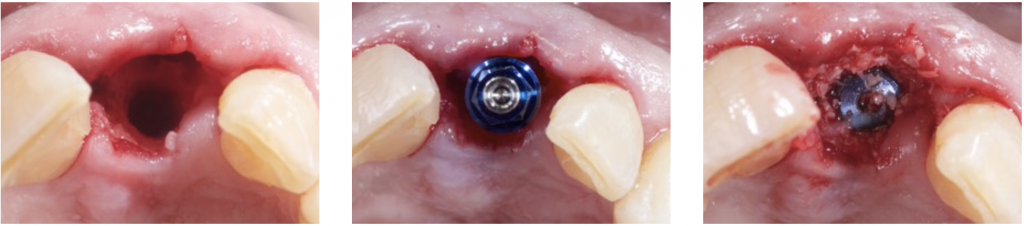

4) DEHISCENCE- TYPE DEFECT: CLASS 3

These defects are characterized by peri-implant dehiscences, in which the adjacent bone walls do not provide the volume stability of the area to be augmented.

In these defects, we will need support for the surrounding soft tissue to achieve stability of the grafted site. Reinforced e-PTFE membranes are mandatory.

Regeneration of class 3 defects step by step:

- Perforation of the cortical bone around the implant (Rompen 1999).

- Application of particulate bone substitute. Autogenous bone mixed with xenograft (50/50) has been reported as a reliable option to add potential osteogenic properties to the graft (Urban 2011).

- Resorbable membranes can be applied over the e-PTFE membrane to facilitate spontaneous wound healing during soft-tissue dehiscence.

- Sutures should be adapted to allow submerged healing.

- De Stavola showed minimal tension (less than 5g) on the flap margins and did not interfere with

primary wound closure.

More tension means more risk and significant complications, so De Stavola proposes a Suspended External-Internal suture (SEI) to reduce marginal flap tension after bone reconstruction (Stavola 2014).

The suture involves only the inner part of the buccal flap to avoid the “killer loop effect.”

After a horizontal mattress and simple suture are performed.

- If we seek a vertical gain, a staged approach is recommended: first regenerate and then place the implants (Artzi 2010).